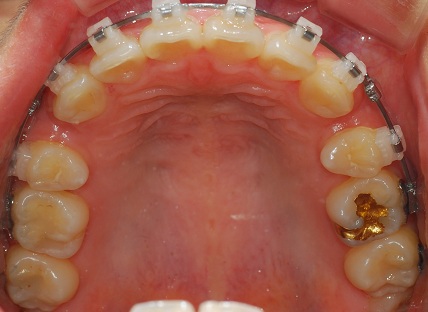

치아 정면사진이에요

발치공간 정말 많이 줄엇죠?

사진을 보면 위에 왼쪽은 스크류가 있고 스크류에 고무줄을 걸었구요

오른쪽은 스크류를 빼고 치아에 있는 장치로만 고무줄을 걸어놨어요.